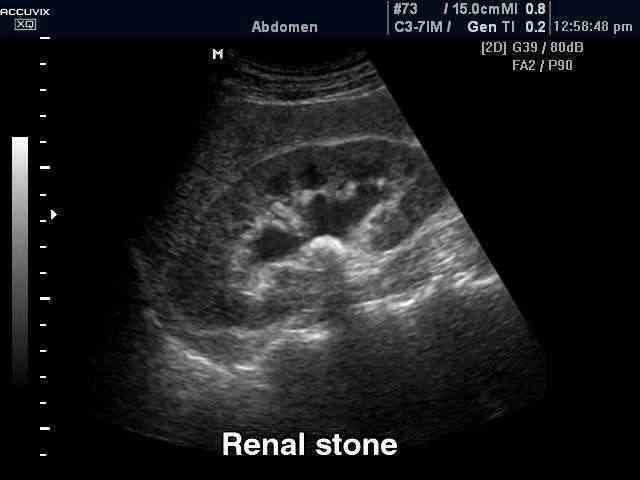

Ретроградная интраренальная хирургия

Передовой малоинвазивный метод удаления конкрементов почек без дополнительных проколов и разрезов с использованием доступа исключительно через естественные мочевые пути. Мочеточник защищается специальным кожухом, по которому в полостную систему почки проводится гибкий эндоскопический инструмент диаметром менее 3 мм – фиброуретеропиелоскоп. С его помощью камень становится доступным для разрушения гольмиевым лазером. Остающиеся крупные фрагменты беспрепятственно извлекаются наружу с использованием специальных нитиноловых корзинок. По окончании операции устанавливается внутренний дренаж и пациент может возвращаться к обычной жизни после выписки на следующий же день из стационара. Данный метод является лидирующим в арсенале ведущих мировых клиник экспертного класса, специализирующихся на лечении мочекаменной болезни.